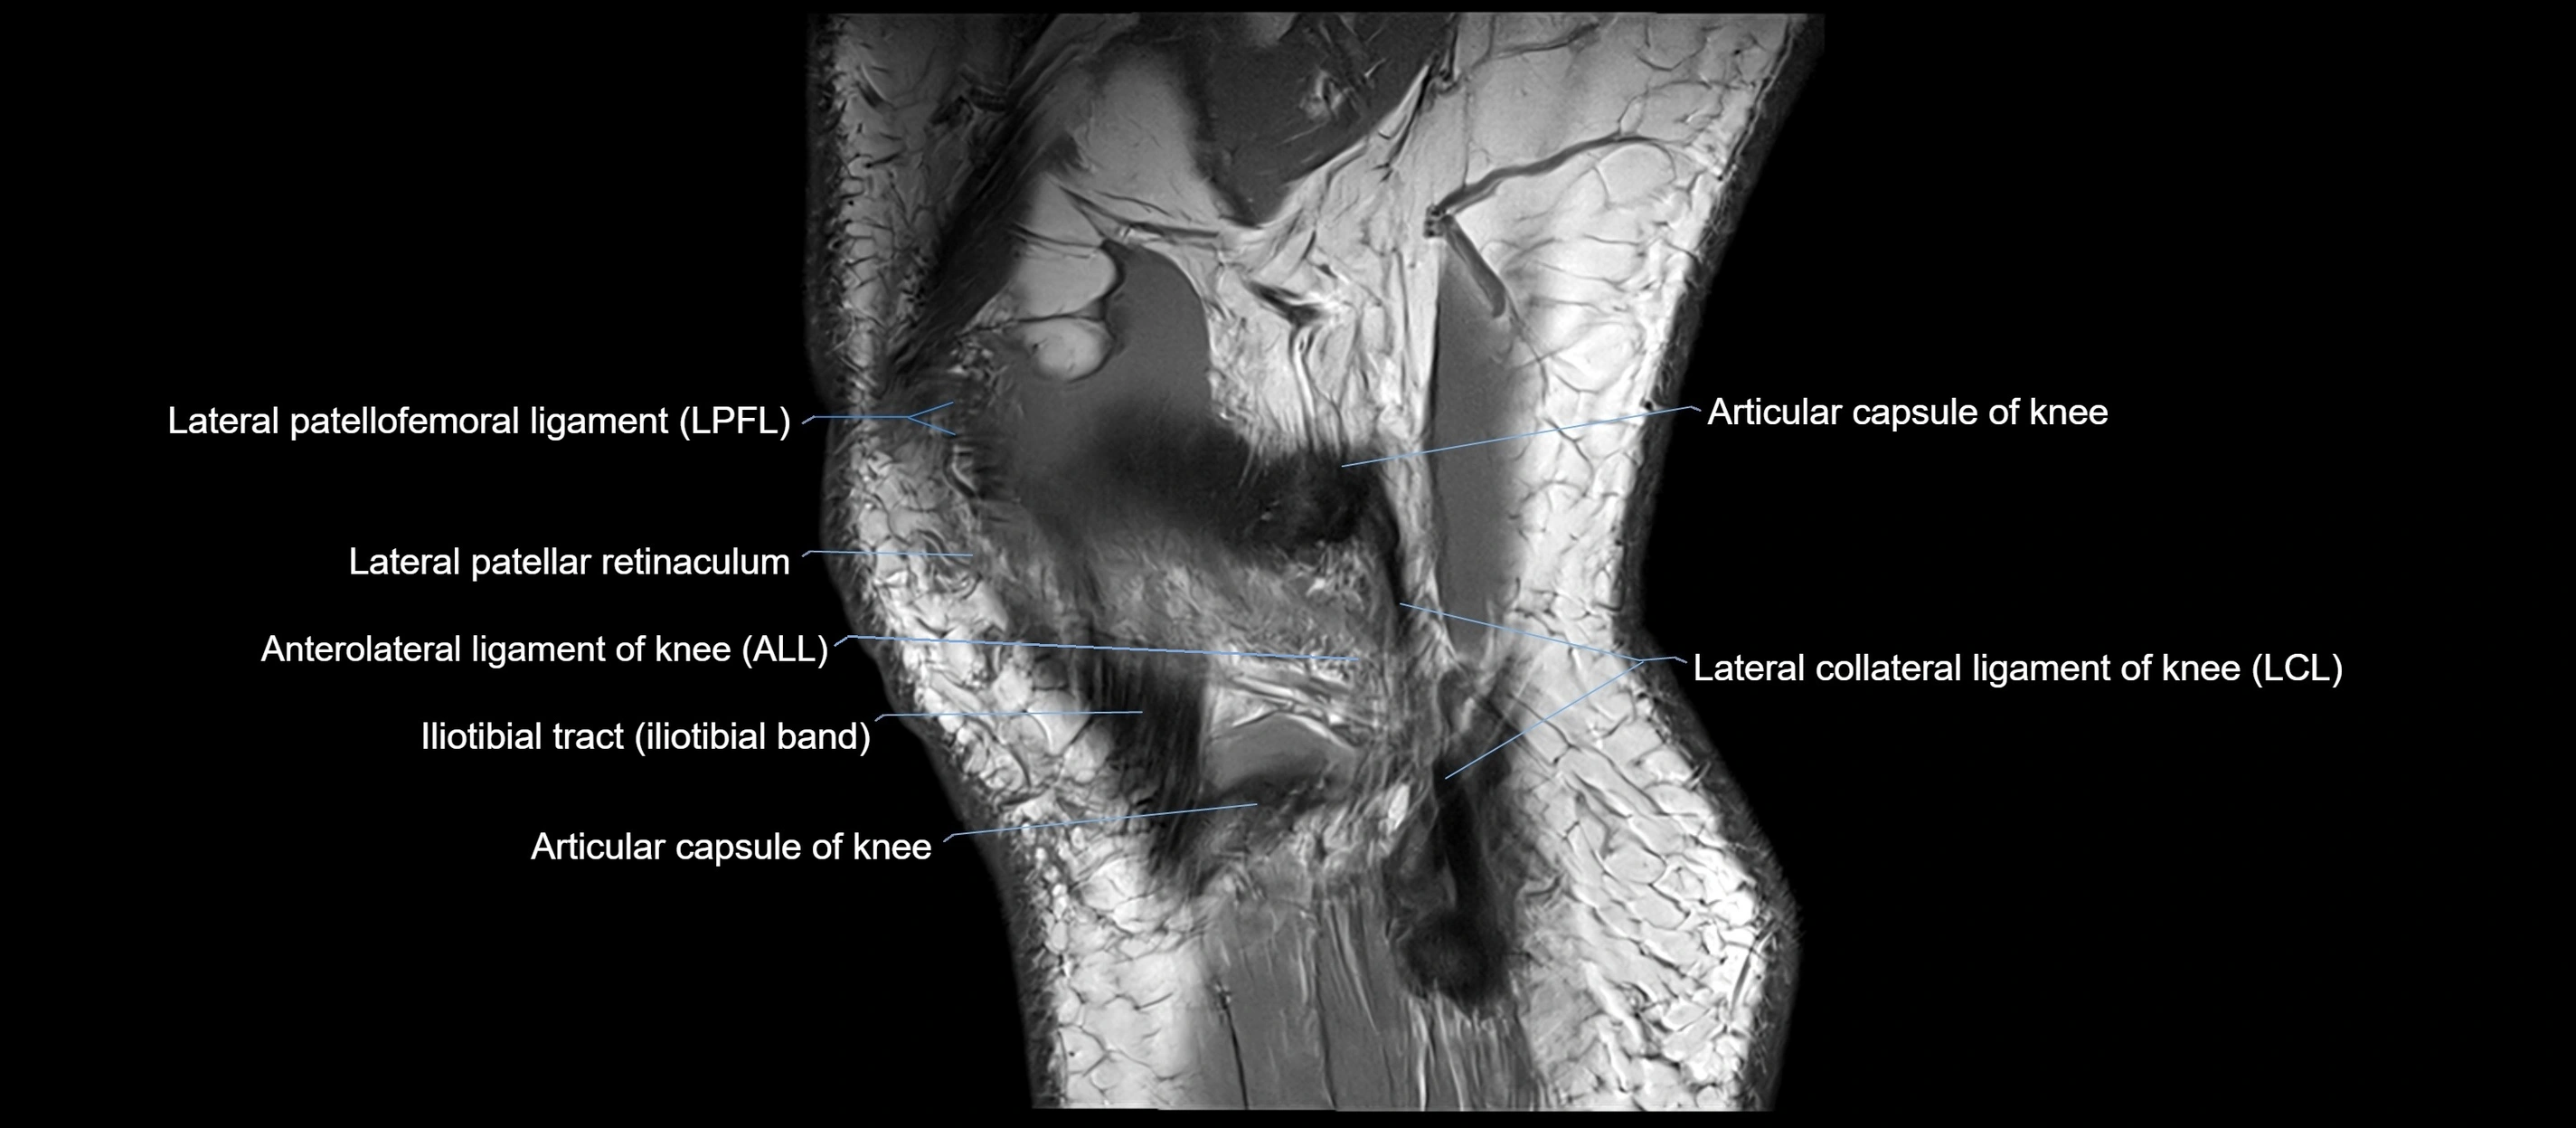

MRI Appearance

T1-weighted images:

• Normal ACL appears as a low-signal band-like structure crossing the intercondylar notch

• Surrounded by intermediate signal synovial fluid and fat planes

T2-weighted images:

• Normal ACL remains low signal

• Partial or complete tears appear as discontinuity, increased signal, or fiber laxity

MRI images

image